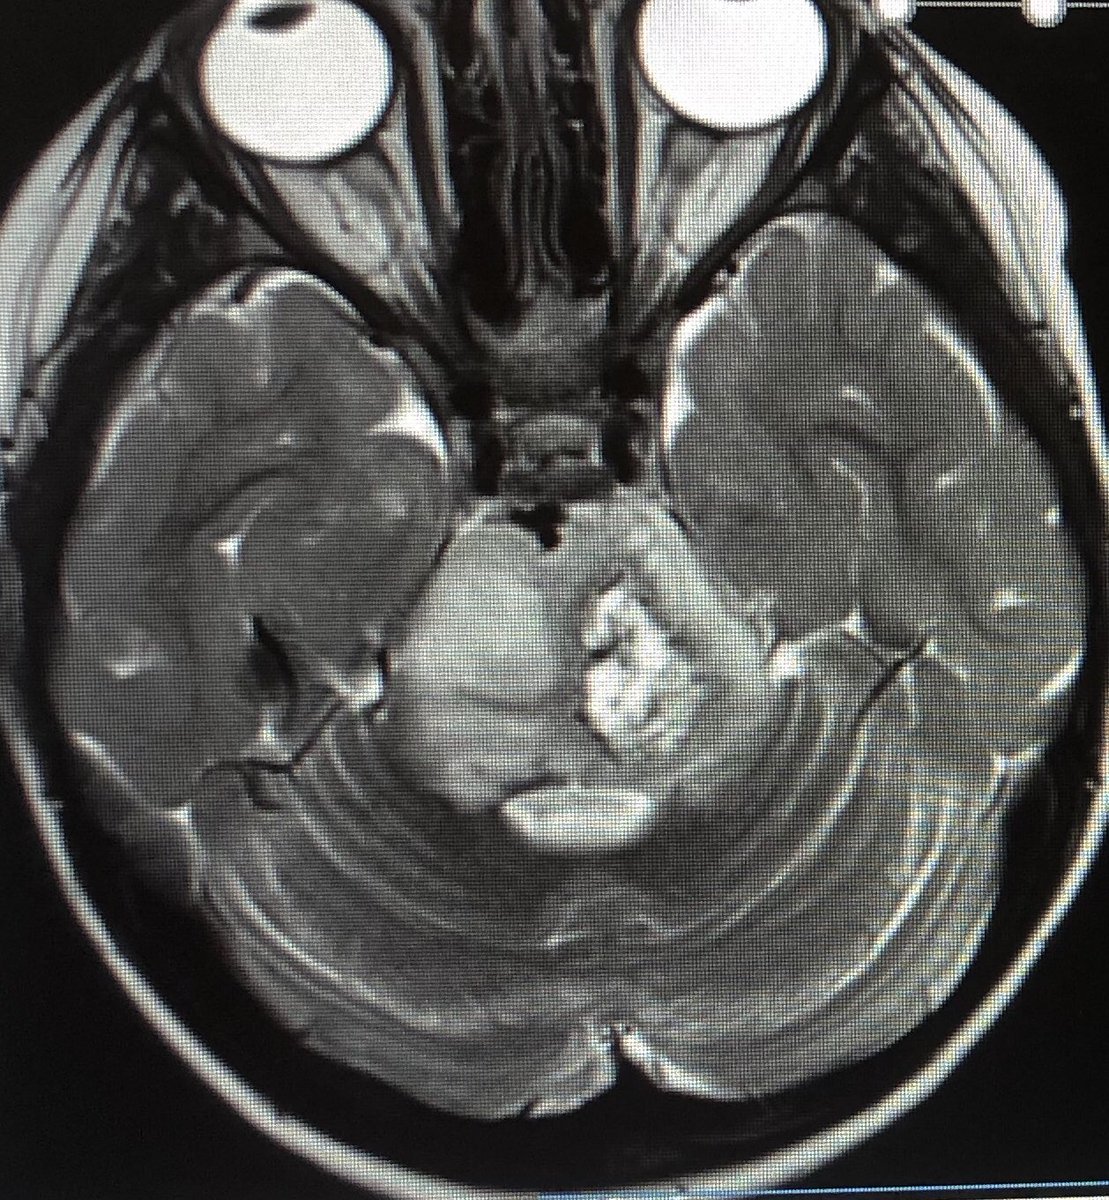

Alright Twitterverse, ultimate challenge, who can suggest how we keep our angel around for a little longer? Someone must know? Gosh we can measure

#marsquakes but yet a brainstem tumour#DIPG is totally baffling? Hit me with your best and brightest. No BS, I don’t have time.pic.twitter.com/AN2nUaFLnP

Show this thread -